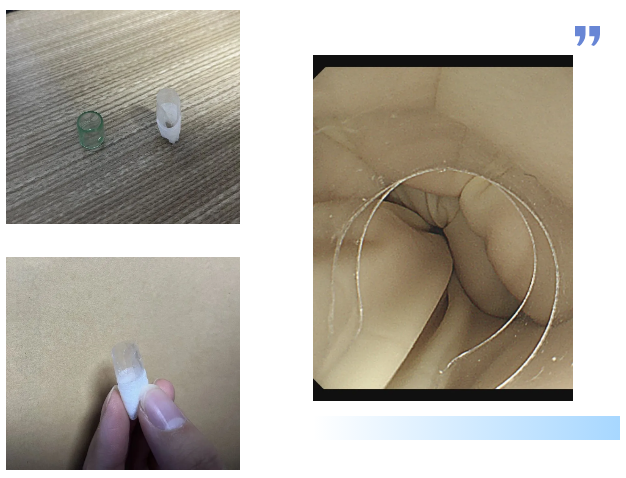

首次取刺失败后,内镜团队紧急召开病例讨论会。大家一致认为,常规透明帽虽能暴露视野,但圆柱形的结构在这种特殊解剖位置下,反而成为了器械操作的阻碍。如何在保持视野清晰的同时,为异物钳创造足够的操作空间,成为了问题的核心。

这时,消化内科主任吕后宁大夫有了一个大胆的想法:对透明帽进行改良。说干就干,吕主任迅速行动起来。他利用现有材料,经过一番巧妙的改造,一个特制的内镜透明帽应运而生。这个小小的豁口,就像是在透明帽上打开了一个“操作窗口”,为异物钳的操作预留了空间。

一切准备就绪后,医生再次为陈女士进行内镜操作。胃镜带着改良后的透明帽缓缓进入食管入口,当鱼刺出现在视野中时,吕主任轻轻旋转胃镜角度,将透明帽的豁口精准对准鱼刺嵌顿的位置。随后缓慢推送胃镜,让鱼刺的一部分稳稳地进入豁口内——此时豁口如同一个“固定卡槽”,将鱼刺牢牢固定住。